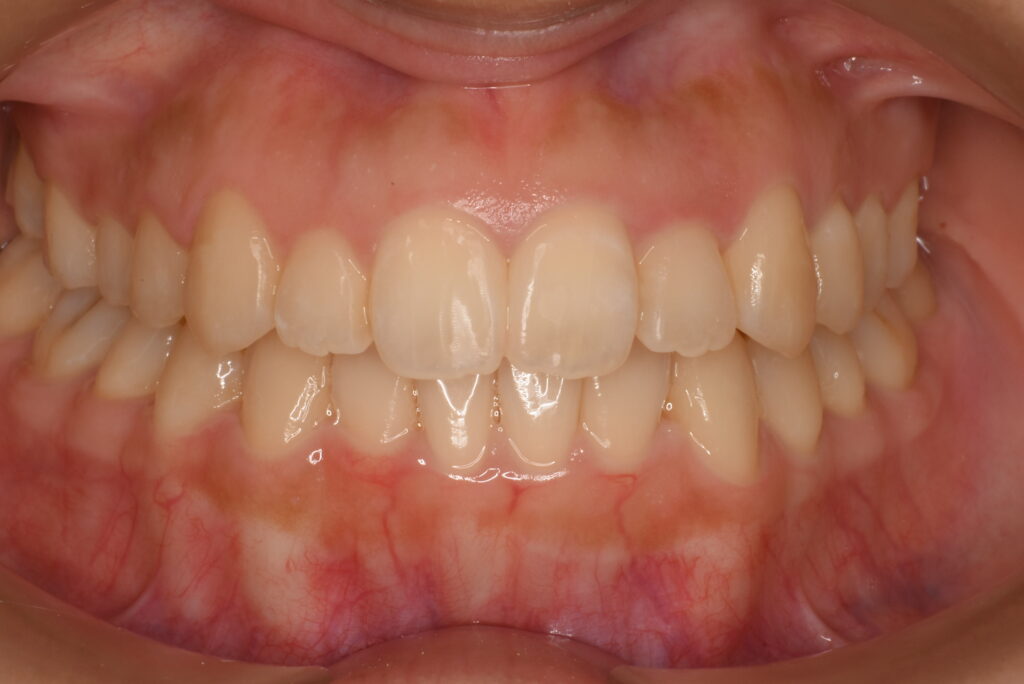

- AFTER

| 治療内容 | 患者様は、歯のガタつきやデコボコした不揃いな歯並び、歯に汚れがつきやすく磨きにくいことを主訴に来院されました。10年以上ぶりの歯科受診で、歯ぐきからの出血(歯肉炎:歯肉病の初期症状)が多く見られたため、インビザライン治療に入る前にブラッシング指導(TBI)や歯周病治療を行い、口腔内環境を整えてから矯正治療を開始しました。 治療開始前には左上の歯の虫歯治療を行い、その後インビザライン治療をスタートしました。抜歯は行わず、非抜歯矯正で歯列を整える方針とし、歯の移動に必要なスペースを確保するために IPR を行いながら治療を進めました。インビザライン治療と並行して歯周病治療も継続し、歯列の改善と口腔内の健康維持の両方を図りました。 |

| 治療期間/通院回数 | 19ヶ月 |